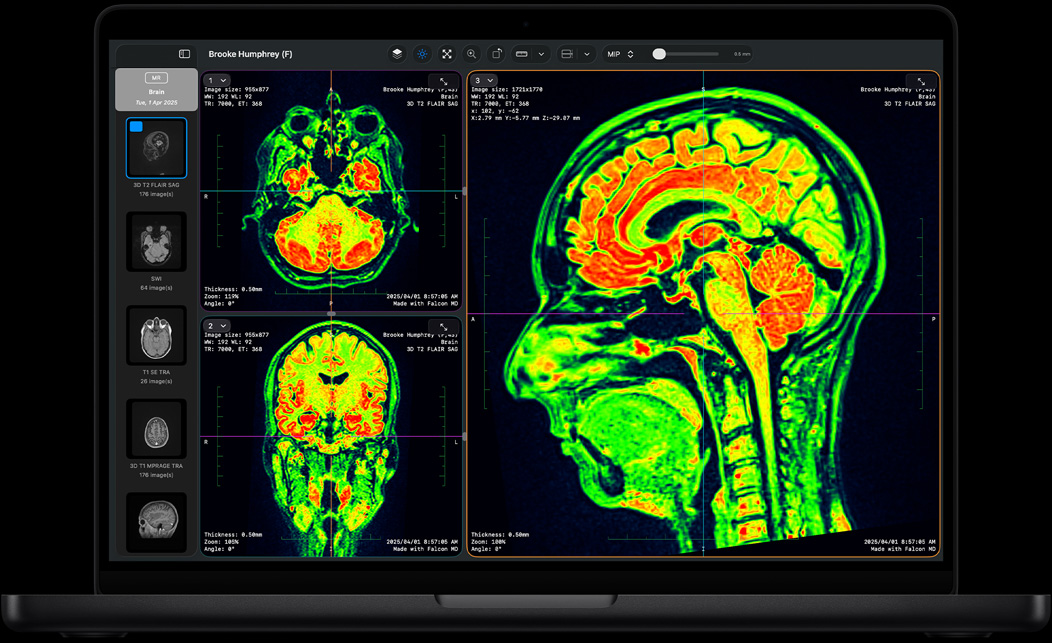

Falcon MD

Mac ir optimizēts darbam ar modernākajām MI aplikācijām un spraudņiem. Darbini tādas attēlu ģenerēšanas aplikācijas kā DiffusionBee, tādas LLM aplikācijas kā Msty Studio un LM Studio un video uzlabošanas aplikācijas kā Topaz Video.

MATLAB, Autodesk AutoCAD, NASA TetrUSS, Oxford Nanopore MinKNOW, OsiriX MD, Shapr3D, SurgicalAR, Vectorworks, Archicad un citas.